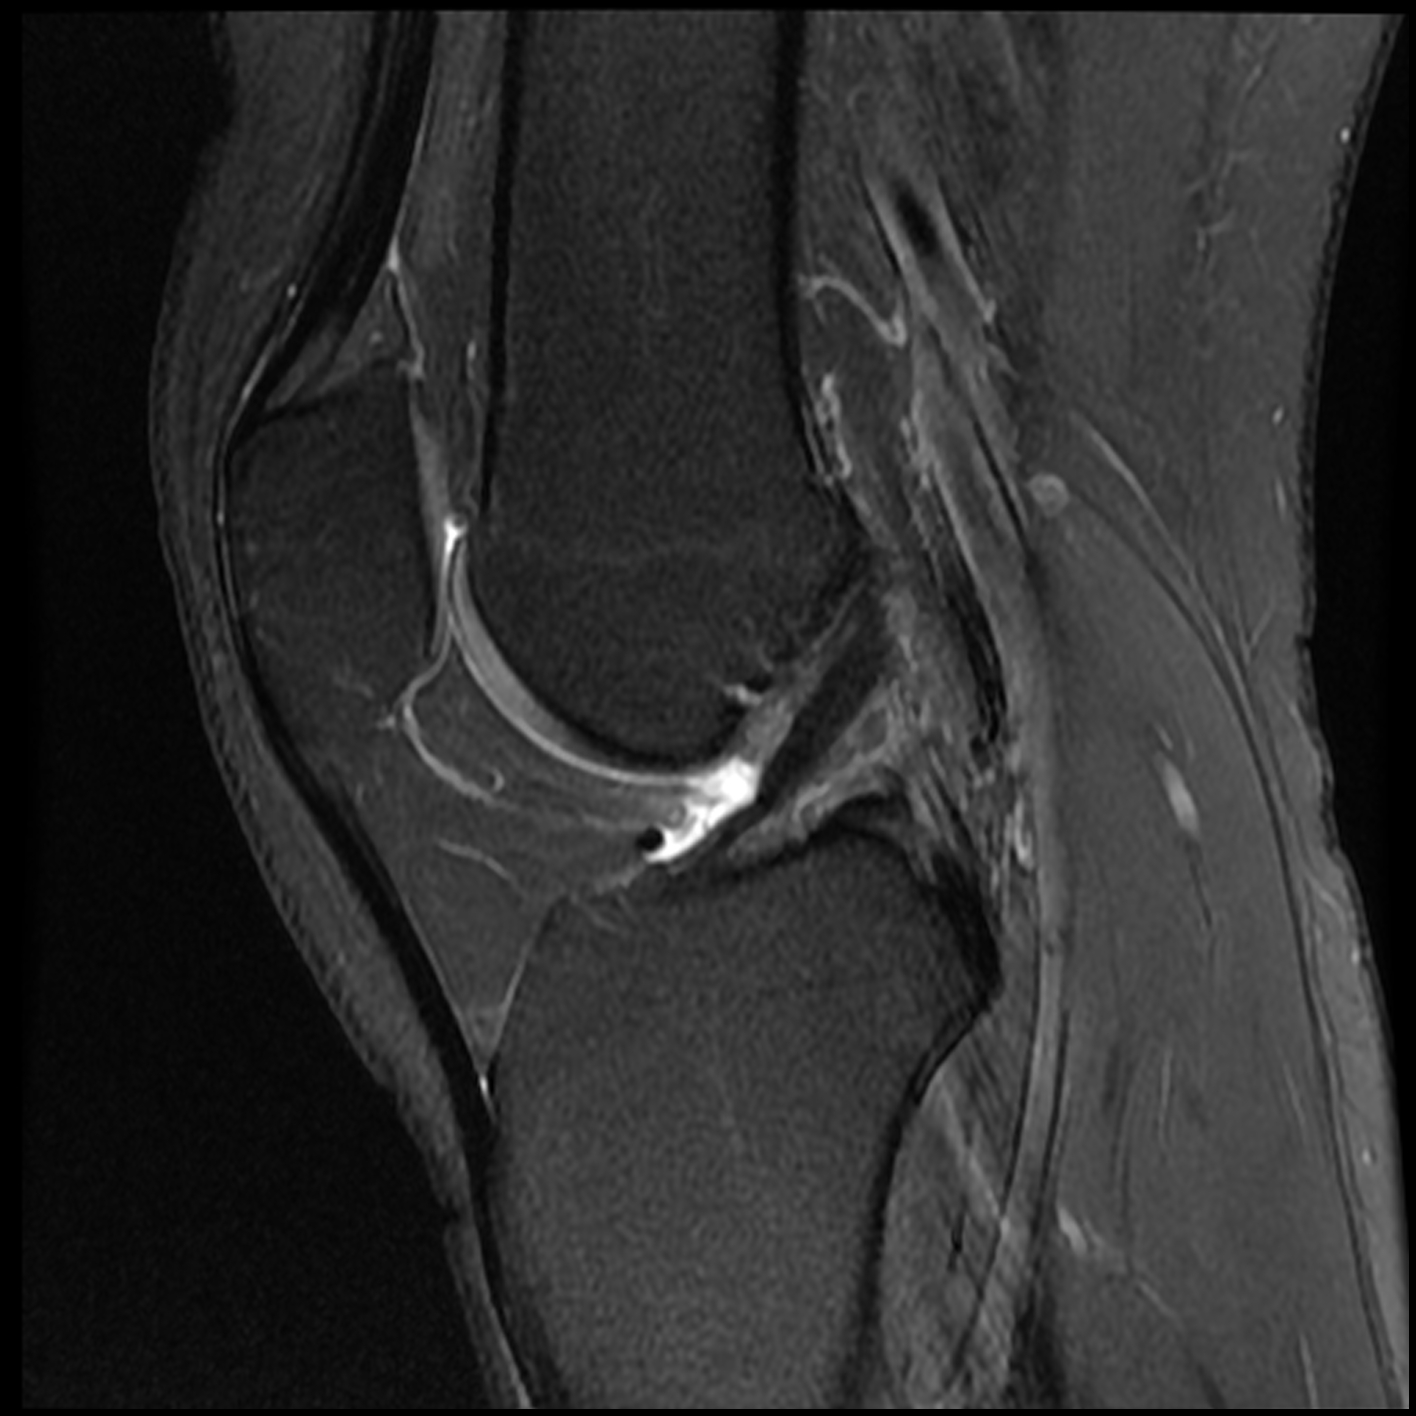

December 2019 MRI

IMPRESSION

- Medial: Nondisplaced horizontal longitudinal tear extending obliquely to the

undersurface of the meniscal body and posterior horn segments. No chondral erosion or thinning. Intact root ligaments. - Intact anterior cruciate ligament. Normal posterior cruciate ligament. Intact medial

lateral supporting structures. - No joint effusion or synovitis. No periarticular muscle injury. No osseous contusion

or stress injury. Minimal fluid in the semimembranosus-medial gastrocnemius bursa. No

frank Baker's cyst.